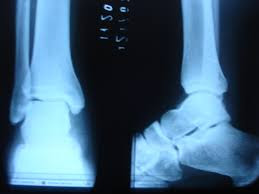

O

diagnóstico será feito mediante a anamnese ou relatos do paciente, no exame físico

e nos exames como RX do local.

No exame físico,

a palpação irá identificar o exato local da lesão e as estruturas envolvidas,

temos testes específicos para mostrar o grau e o tipo de lesão ligamentar. No caso

do RX, irá excluir a possibilidade de fraturas no local.